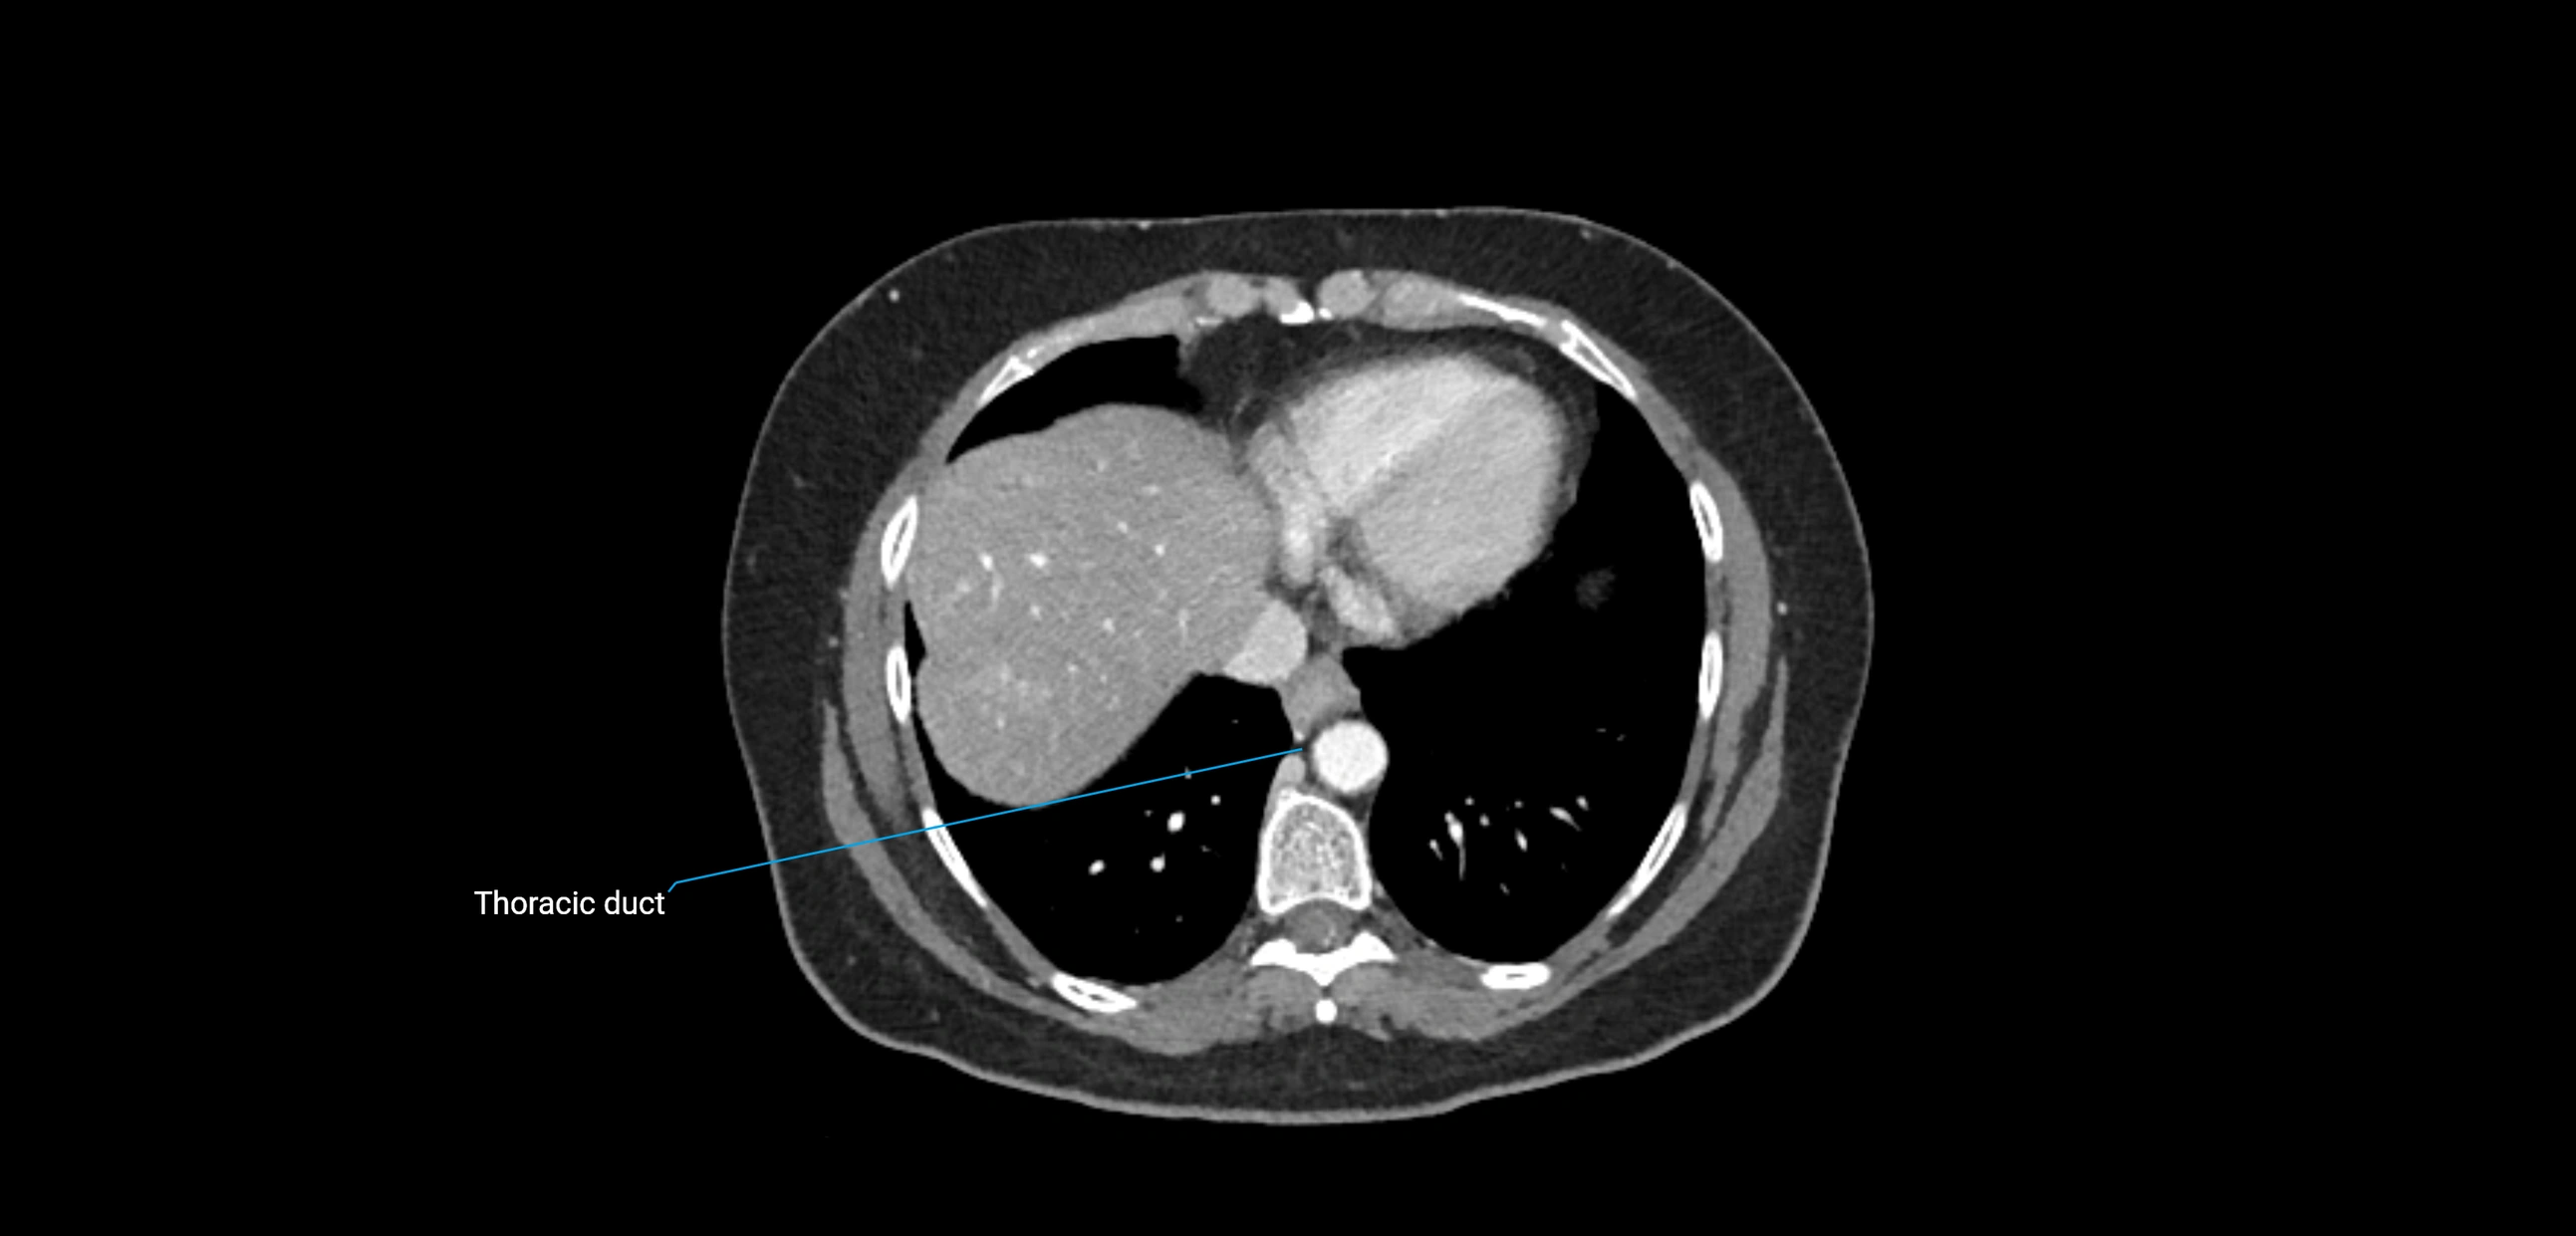

CT Appearance

CT Post-Contrast:

• Normal nodes enhance homogeneously

• Malignant nodes may show heterogeneous enhancement, central necrosis, or conglomerate formation

• Size >1 cm short axis is suspicious, though morphology and distribution are equally important

CT Venography (CTV):

• Demonstrates nodal encasement or compression of adjacent vessels (aorta, IVC, renal veins)

• Useful in staging testicular and ovarian malignancies

• Provides 3D reconstructions for retroperitoneal lymph node dissection planning